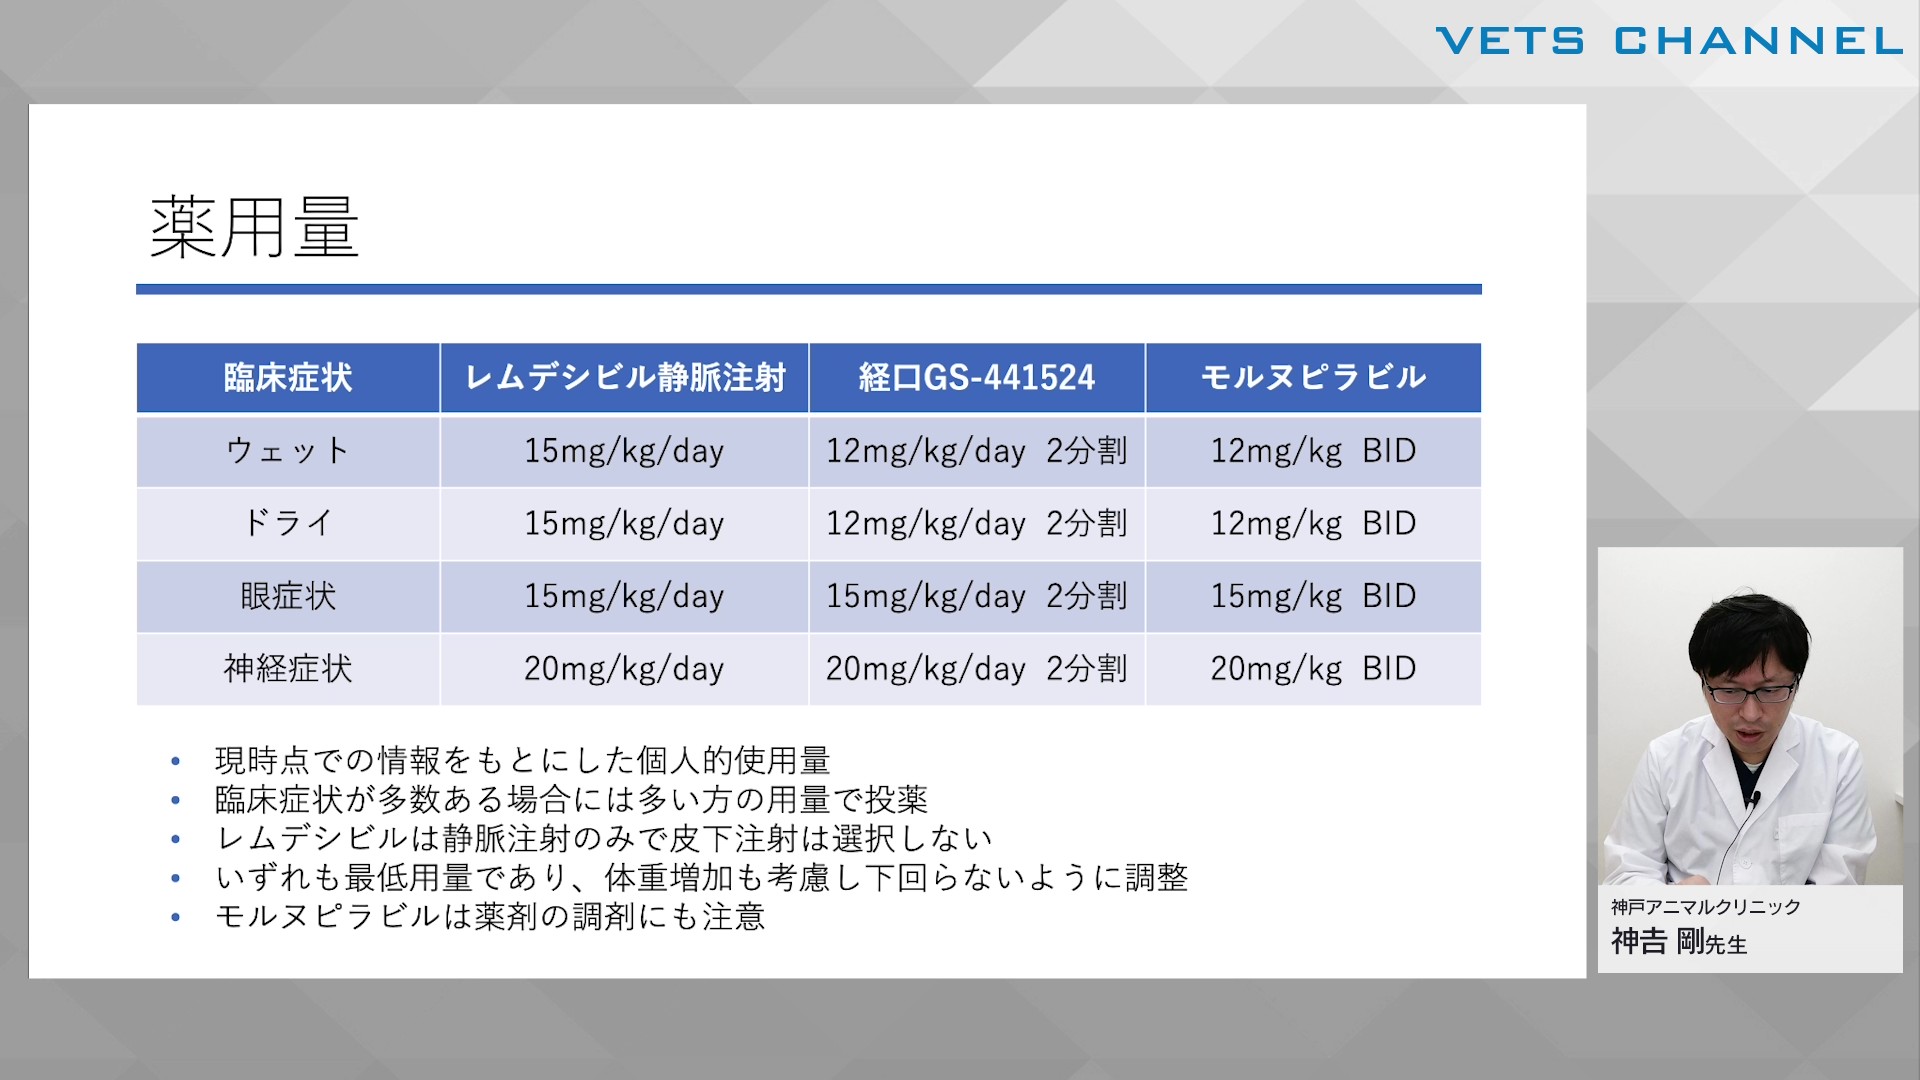

“猫ならでは”を知る 特徴的な疾患の診断と治療 第3回:感染症

- セミナー

- 内科全般

- 猫

神吉 剛先生 (神戸アニマルケアクリニック)

72分

2025/08/15